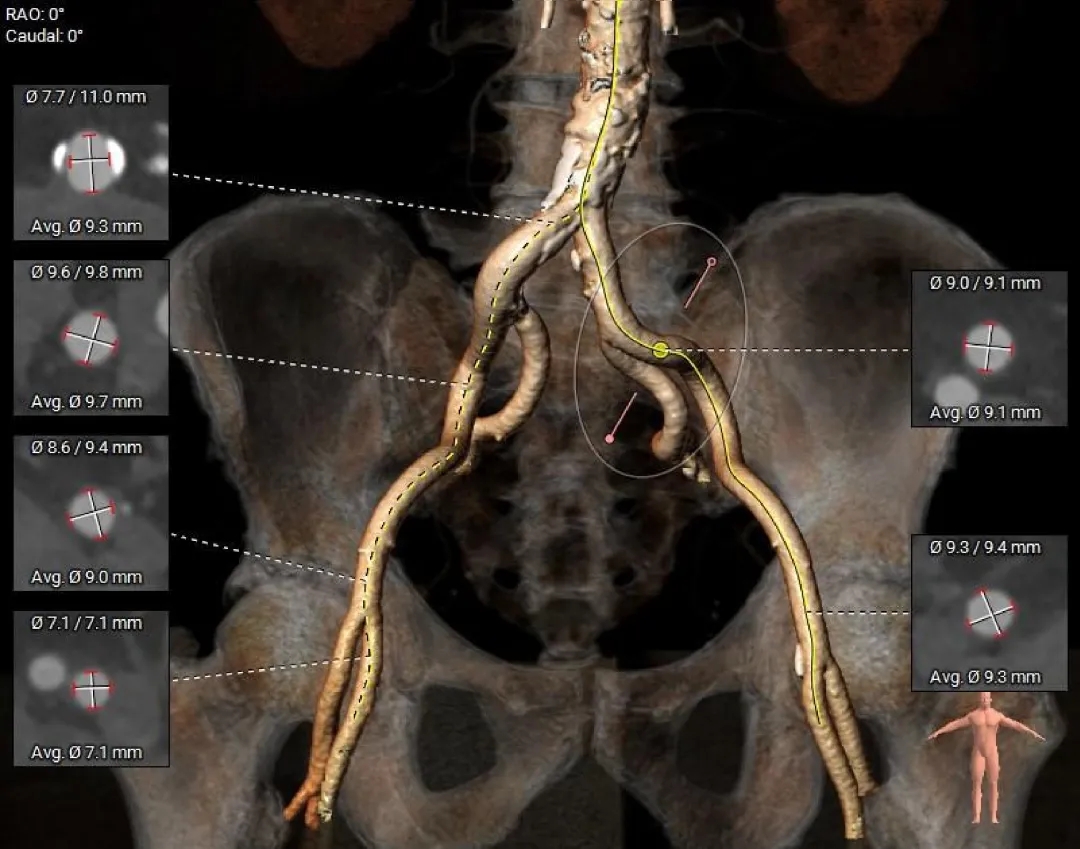

外周入路评估

-

髂动脉轻微迂曲

腹主动脉可见钙化斑块

血管内径充足